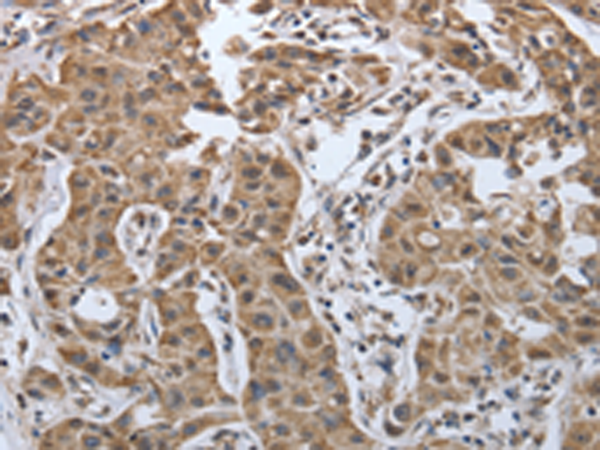

分类: 科研抗体货号: P11313别名: PDGF1, PDGF-A应用: IHC反应种属: Human, Mouse, Rat